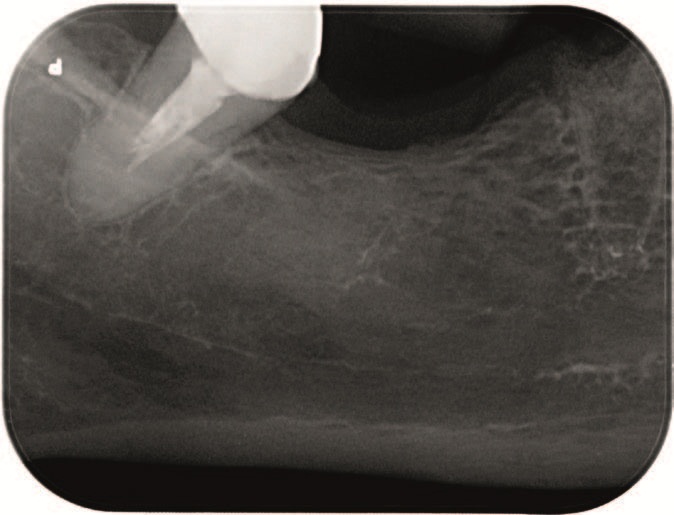

Рис. 1 – Передоперационный внутриротовий рентген, где кариес корня видно на зубе 4.5.

Рис. 7 – Послеоперационный внутриротовой рентген, показывающий адекватное и полное заполнение лунки.